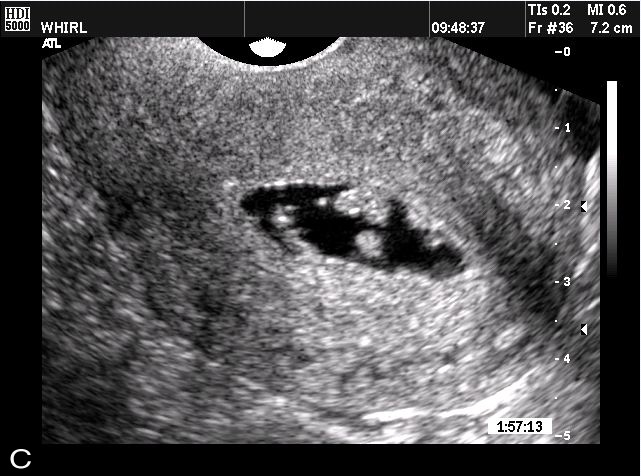

• توجد حالات نادرة حيث تظهر أعراض الحمل قبل غياب الدورة بشكل واضح، وتكون سببًا في التشخيص المبكر لحمل خارج الرحم أو حالات مشابهة.